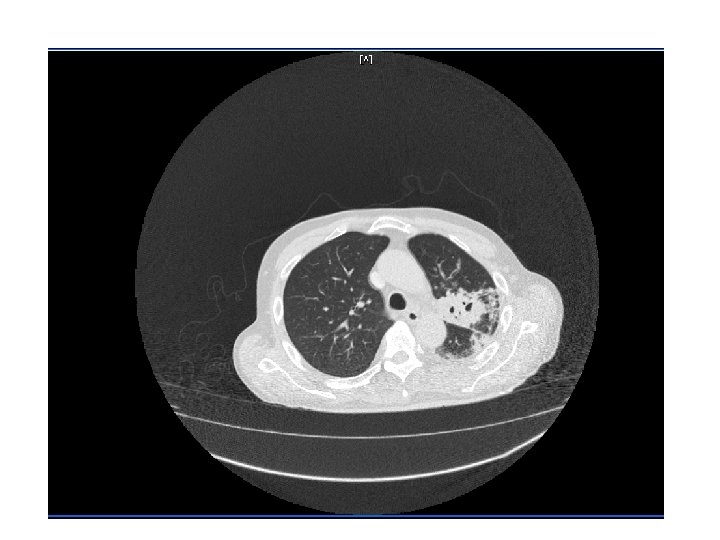

CT Chest • Multiple cavitary lesions • Largest left lung apex 3. 8 x 4. 7 cm with nodular thickened wall • Smaller cavitary lesions in L lung base • R lung: smaller areas of ground-glass opacities with areas of tree in bud appearance.